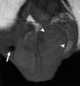

Postinflammatory scrotal pearl